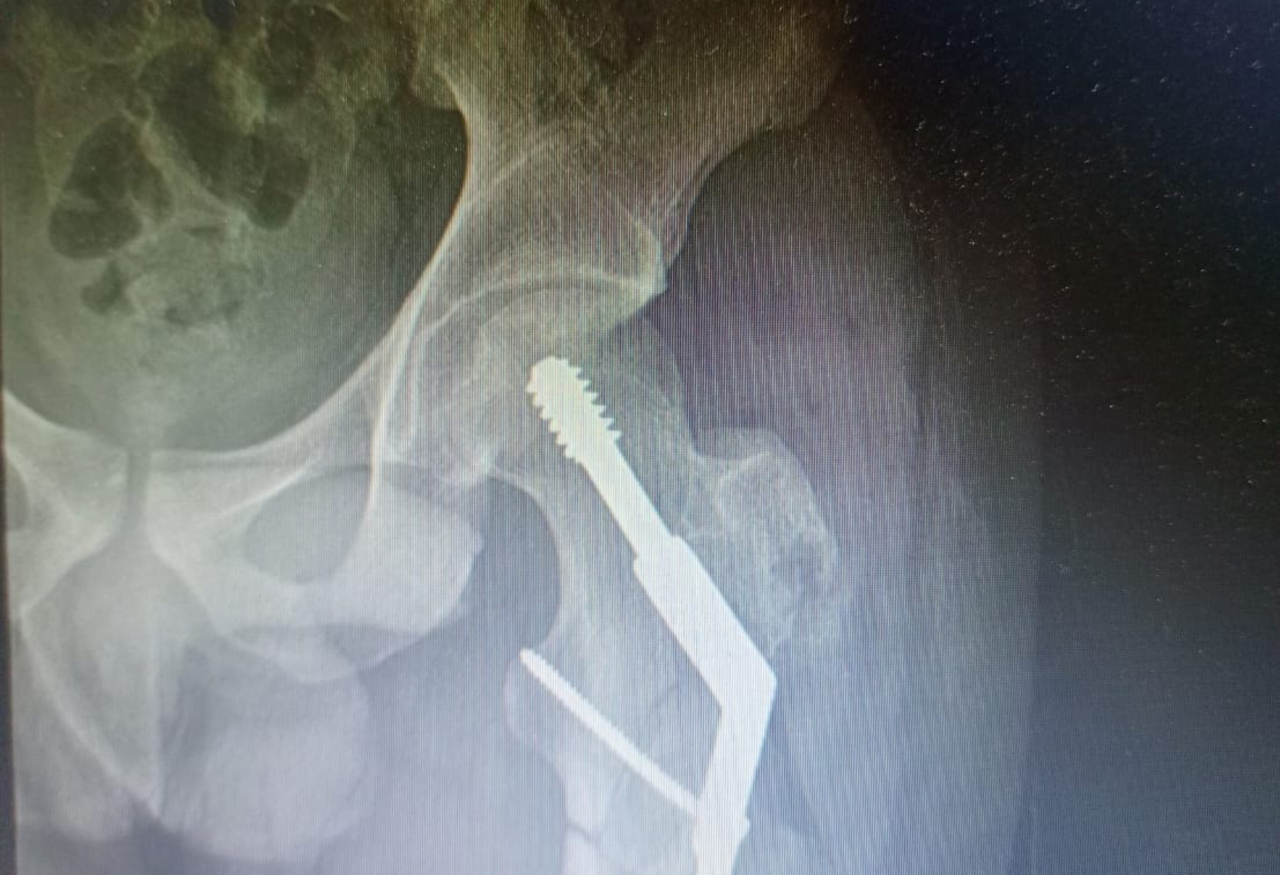

2

Cirugía exitosa

Se realiza reducción y aplicación de un DHS para estabilizar la fractura